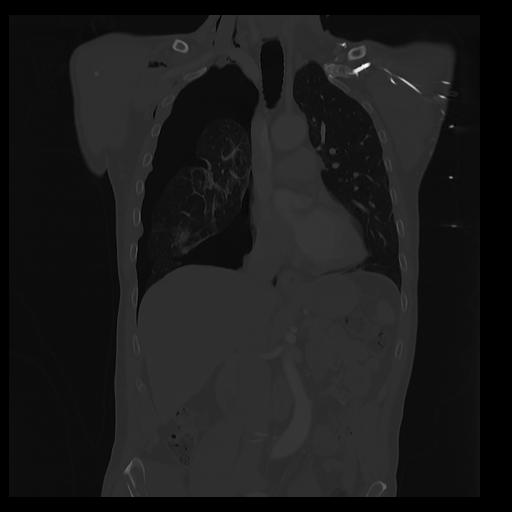

32 PULMON,CE,Coronal,3.000,PULMON,Coronal,